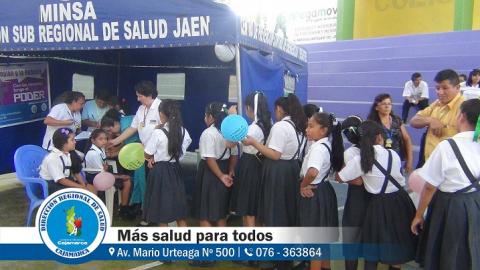

JAÉN: REALIZAN CAMPAÑA DE VACUNACIÓN PARA CONTROLAR ENFERMEDADES PREVENIBLES

Wilmer Vicente Abad, Coordinador de Inmunizaciones, dio a conocer que “los padres y madres de familia tienen la oportunidad de vacunar a sus hijos de acuerdo al calendario de vacunación hasta el 30 de abril, fecha en que culmina esta campaña cuyo lanzamiento inició el pasado 17 de marzo”.

Así mismo, informó que “no importa la edad, todos tienen la posibilidad de vacunarse y protegerse de enfermedades que en algunos de los casos pueda dejar secuelas y afectar el desarrollo físico y personal e inclusive causar la muerte”.

Las vacunas contribuyen a mejorar el nivel de salud de la población mediante la prevención y control de enfermedades; entre ellas la Difteria, Tos Ferina, Sarampión, Rubeola, Tétanos, Hepatitis B, Influenza, VPH.

En ese sentido, el coordinador de inmunizaciones, instó a la población a visitar los establecimientos de salud para que puedan recibir sus vacunas de acuerdo al esquema nacional establecido por el Ministerio de Salud (MINSA), y en el caso de la vacuna del VPH, que se le aplica a las niñas del quinto grado de primaria, deberán esperar al personal de salud, que estará visitando las instituciones educativas.